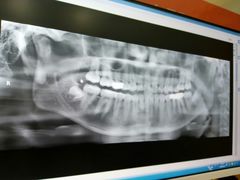

• 土豆口腔(凤凰北总店)

• -土豆口腔(凤凰北总店)